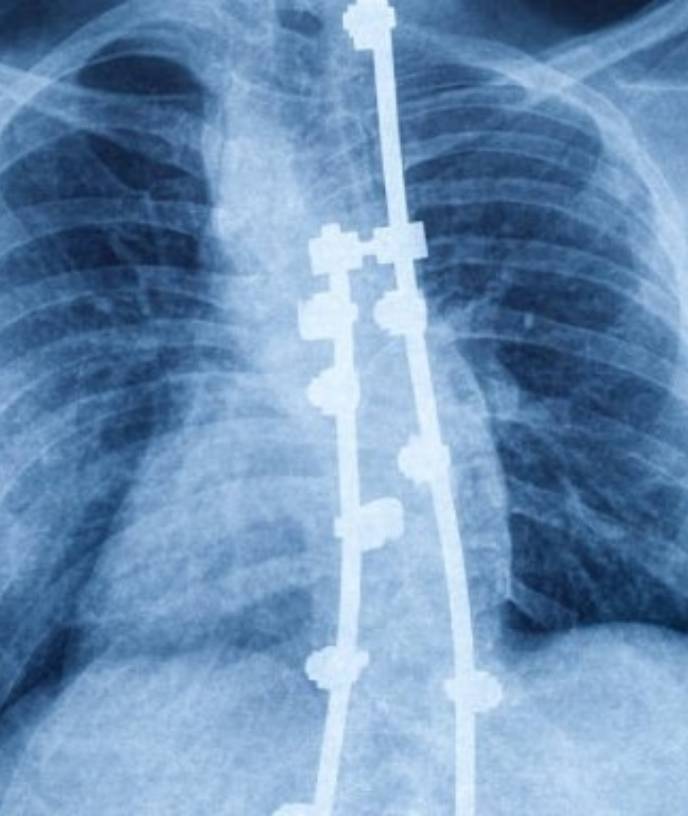

Spine surgery treats back issues like disc problems, fractures & deformities, restoring mobility & relief.